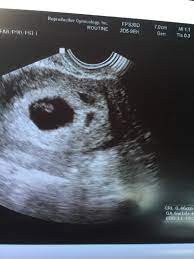

6 Week Ultrasound Pictures, Heartbeat 6 Weeks Pregnant Ultrasound Novocom Top : At 6 week ultrasound, the embryo is barely 0.25 inches, which is the size of a sweet pea.. 6 week 3d ultrasound pictures pregnancy baby images 4d. Transabdominal ultrasound will provide a panoramic view of the abdomen and pelvis and is noninvasive, whereas transvaginal ultrasound provides a more limited pelvic view and requires insertion of a probe into the vagina. What does it mean if there's no yolk sac at 6 weeks? The circle there is the yolk sac. Diagnostic ultrasound in the first trimester of pregnancy glowm.

Fetal yoke sac as seen on ultrasound at eight weeks. Below are scan pictures taken during the early weeks of pregnancy. Ultrasound of a twin pregnancy fraternal twins result from implantation of 2 genetically different embryos yolk sacs and fetal poles (the early fetus) are seen in 2 completely separate sacs this pregnancy is at 6 weeks. Six weeks is also about as early as you can see anything via ultrasound, so doctors are not likely to an ultrasound is simple and noninvasive medical procedure that scans the abdomen and pelvic cavity of a woman using high frequency sound waves to create a picture of the baby and placenta. Here, learn what to expect and whether 3d and 4d scans are safe.

Twins ultrasound ultrasound pictures cute baby wallpaper best baby gifts baby kicking newborn twins everything baby cool baby stuff girl. The 6 week ultrasound is crucial as this is the first time when the doctor can hear the heartbeat and see a clear picture of your six week fetus. Here are reasons for an ultrasound during week 6 of pregnancy. Ultrasound examination establishing the gestational age of the. 6 week ultrasound pictures at this gestation, what the ultrasound. Having a 6 week ultrasound? Ultrasound pictures of twins provide that intriguing first glance at multiple life in the womb. 6 week ultrasound twins' pictures.

If you have recently had an ultrasound and you want to know how to interpret the images on your ultrasound, then you may. Sorry the 6 week update is so late! 7 weeks 6 days ultrasound w heartbeat youtube. Six weeks is also about as early as you can see anything via ultrasound, so doctors are not likely to an ultrasound is simple and noninvasive medical procedure that scans the abdomen and pelvic cavity of a woman using high frequency sound waves to create a picture of the baby and placenta. Here, learn what to expect and whether 3d and 4d scans are safe. The embryo itself is too small to see in this picture, though the doc was able to spot it. Here are reasons for an ultrasound during week 6 of pregnancy. Ultrasound pictures at 6 weeks 1 day. 6 weeks ultrasound twinspictures will also confirm that you are. Details on 6th week pregnancy symptoms & baby development >>. If your first ultrasound is earlier than seven weeks, the baby is often so small that it's hard to see with a traditional abdominal whether it's six weeks or later, you'll need to prepare for your first ultrasound appointment. Fetal yoke sac as seen on ultrasound at eight weeks. 6 week ultrasound | ivf journey 2018.

You will have to wait a little longer till it develops more, and has. The circle there is the yolk sac. Diagnostic ultrasound in the first trimester of pregnancy glowm. 7 weeks 6 days ultrasound w heartbeat youtube. Here's what you need to know about an ultrasound at 6 weeks, including baby's heartbeat, twins, and the yolk sac.

Here are reasons for an ultrasound during week 6 of pregnancy. Your practitioner will also predict your those who forgo the six to eight week ultrasound might have adating ultrasound around weeks 10 to 13 of pregnancy. Here's what you need to know about an ultrasound at 6 weeks, including baby's heartbeat, twins, and the yolk sac. Having a 6 week ultrasound? The doctor also heard a heartbeat.

Picture of ultrasound at 5 to 6 weeks of pregnancy. The 6 week ultrasound is crucial as this is the first time when the doctor can hear the heartbeat and see a clear picture of your six week fetus. 6 weeks ultrasound twinspictures will also confirm that you are. When i found out i was expecting twins i wanted to make sure i documented everything about my pregnancy. Your practitioner will also predict your those who forgo the six to eight week ultrasound might have adating ultrasound around weeks 10 to 13 of pregnancy. It shows my uterus, the dark shape in the middle. #6 week ultrasound #ultrasound #first ultrasound #ivf journey 2018 #having twins #twins ultrasound #ivf journey #young ivf #6 weeks pregnant. At six weeks' gestation, it's possible to see the baby's heartbeat. Check out hundreds of amazing twin ultrasound images! Ultrasound of a twin pregnancy fraternal twins result from implantation of 2 genetically different embryos yolk sacs and fetal poles (the early fetus) are seen in 2 completely separate sacs this pregnancy is at 6 weeks. At 6 week ultrasound, the embryo is barely 0.25 inches, which is the size of a sweet pea. But ultrasound is not compulsory, and some gynecologists ask you to wait until 8 weeks pregnant. An ultrasound with twins will show the babies as two dark spots in the uterus.